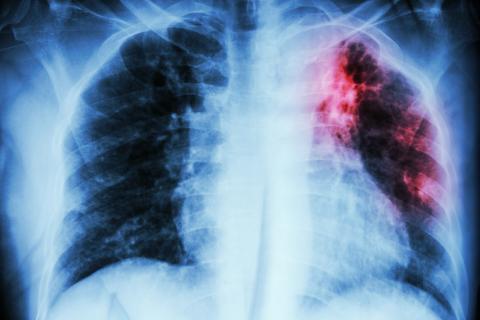

Scope of problem More than 60 years after the development of effective antimycobacterial therapy, tuberculosis (TB) remains a significant problem in British Columbia. Provincial TB rates exceed the Canadian average,... Read More

Canada is a favored destination for immigrants from many parts of the world. In 2006 the World Health Organization reported that 83% of all tuberculosis cases occurred in three geographical regions—Africa, Southeast... Read More

World Tuberculosis Day, recognized on 24 March of each year, raises public awareness about tuberculosis (TB). The global TB epidemic causes several million deaths per year, mostly in the developing world where HIV... Read More